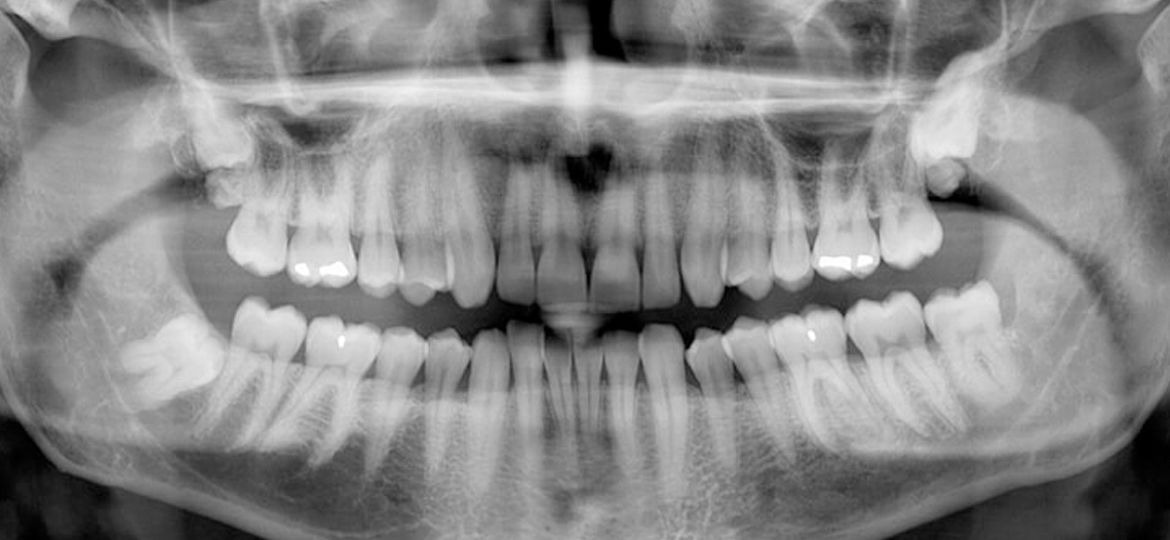

Panoramic dental X-rays capture a comprehensive image of the mouth in a single scan. Unlike traditional X-rays that focus on specific areas, this technique provides a broader perspective, helping dental specialists detect concerns like impacted teeth, jawbone irregularities, cysts, tumors, and even sinus issues. Its accuracy and convenience make it a widely used diagnostic tool for both preventive care and advanced treatment planning.